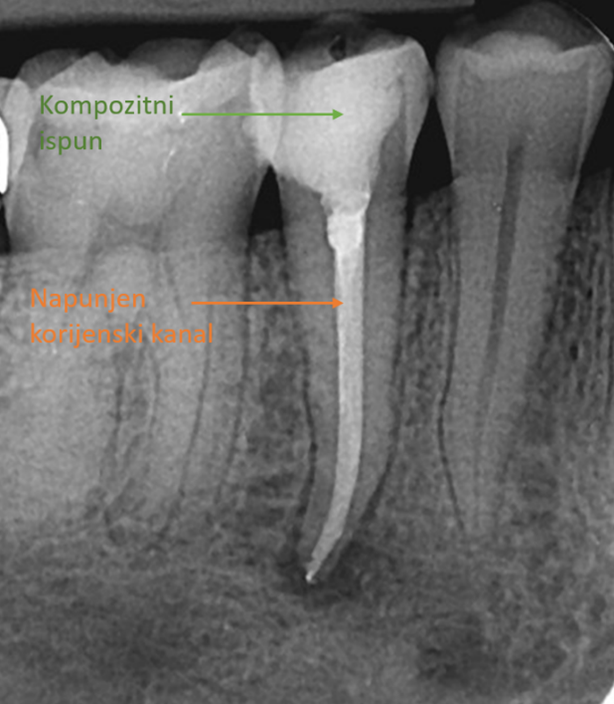

U tu svrhu se, osim instrumenata za mehaničko čišćenje, koriste snažni dezinficijensi, a zatim se očišćeni korijenski kanal puni biokompatibilnim materijalom kojemu je cilj zabrtviti prazan prostor koji je ostao kako se baketerije ne bi imale gdje naseliti i ponovno izazvati infekciju.

Saniran zub: učinjeno je liječenje korijenskog kanala, očišćen karijes te postavljen kompozitni ispun

Nakon završenog liječenja zub je „iznutra zdrav“, ali često oslabljen od karijesa, pa ga je preporučljivo zaštititi kvalitetnim ispunom ili krunicom. Tako se vraća njegova funkcija i estetika, a zub se štiti od mogućeg puknuća.